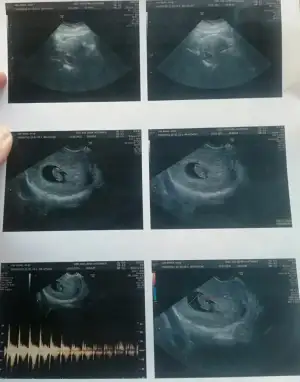

vajinal muayene 8. hafta görüntülerimiz bizimkinide yorumlar mısınız

Eklentiler

• bebişiiim.webp

bebişiiim.webp

29,9 KB · Görüntüleme: 63